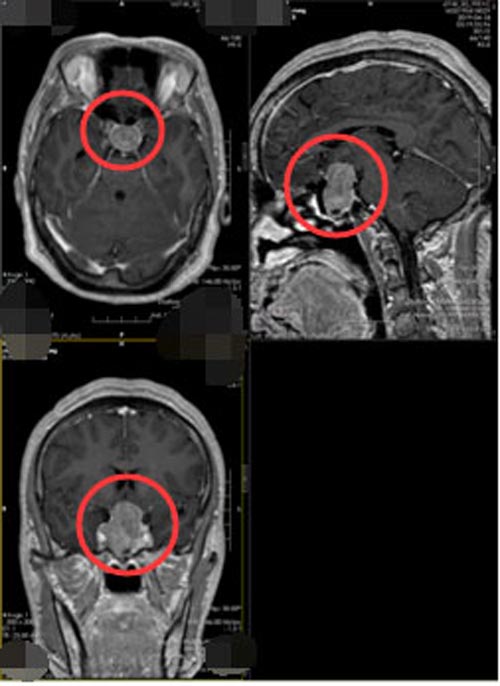

完善相关的术前准备后,张大姐在内镜下“经鼻垂体瘤切除的微创手术”,手术过程顺利,出手术室时就已经苏醒,视力视野无异常。术后2天康复出院,生长激素由原来的243.40ug/L下降到正常范围的 4.63ug/L,她自己也感觉到四肢有明显的松解。

▲手术后